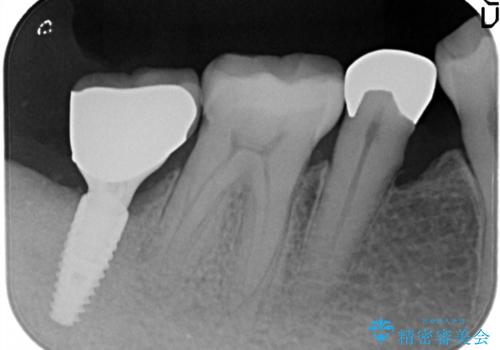

- 奥歯が痛いことを主訴に来院されました。

重度の歯周病により保存困難と診断し、抜歯後にインプラント治療を行いました。

抜歯後十分な骨の回復が認められず、単独の骨増生を行った後にインプラントを埋入しました。

インプラント埋入時に骨が足りない場合にはインプラント埋入前に骨増生を行います。また、インプラント周囲の角化歯肉が不足した場合は角化歯肉の移植も行うことがあります。

どちらの治療もインプラントの長期予後を高めるために必要な治療です。